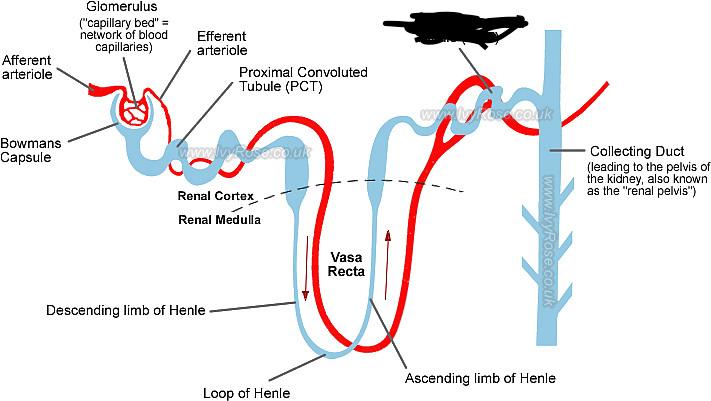

Afferent/efferent arteriole

Collecting duct

Descending/Ascending loop (of nephron)

Distal (convoluted) tubule

Glomerular capsule (=Bowman's capsule)

Glomerulus (=glomerular capillaries)

Juxtaglomerular apparatus

Nephron

Peritubular capillaries

Proximal (convoluted) tubule

Renal corpuscle

Renal cortex

Renal medulla